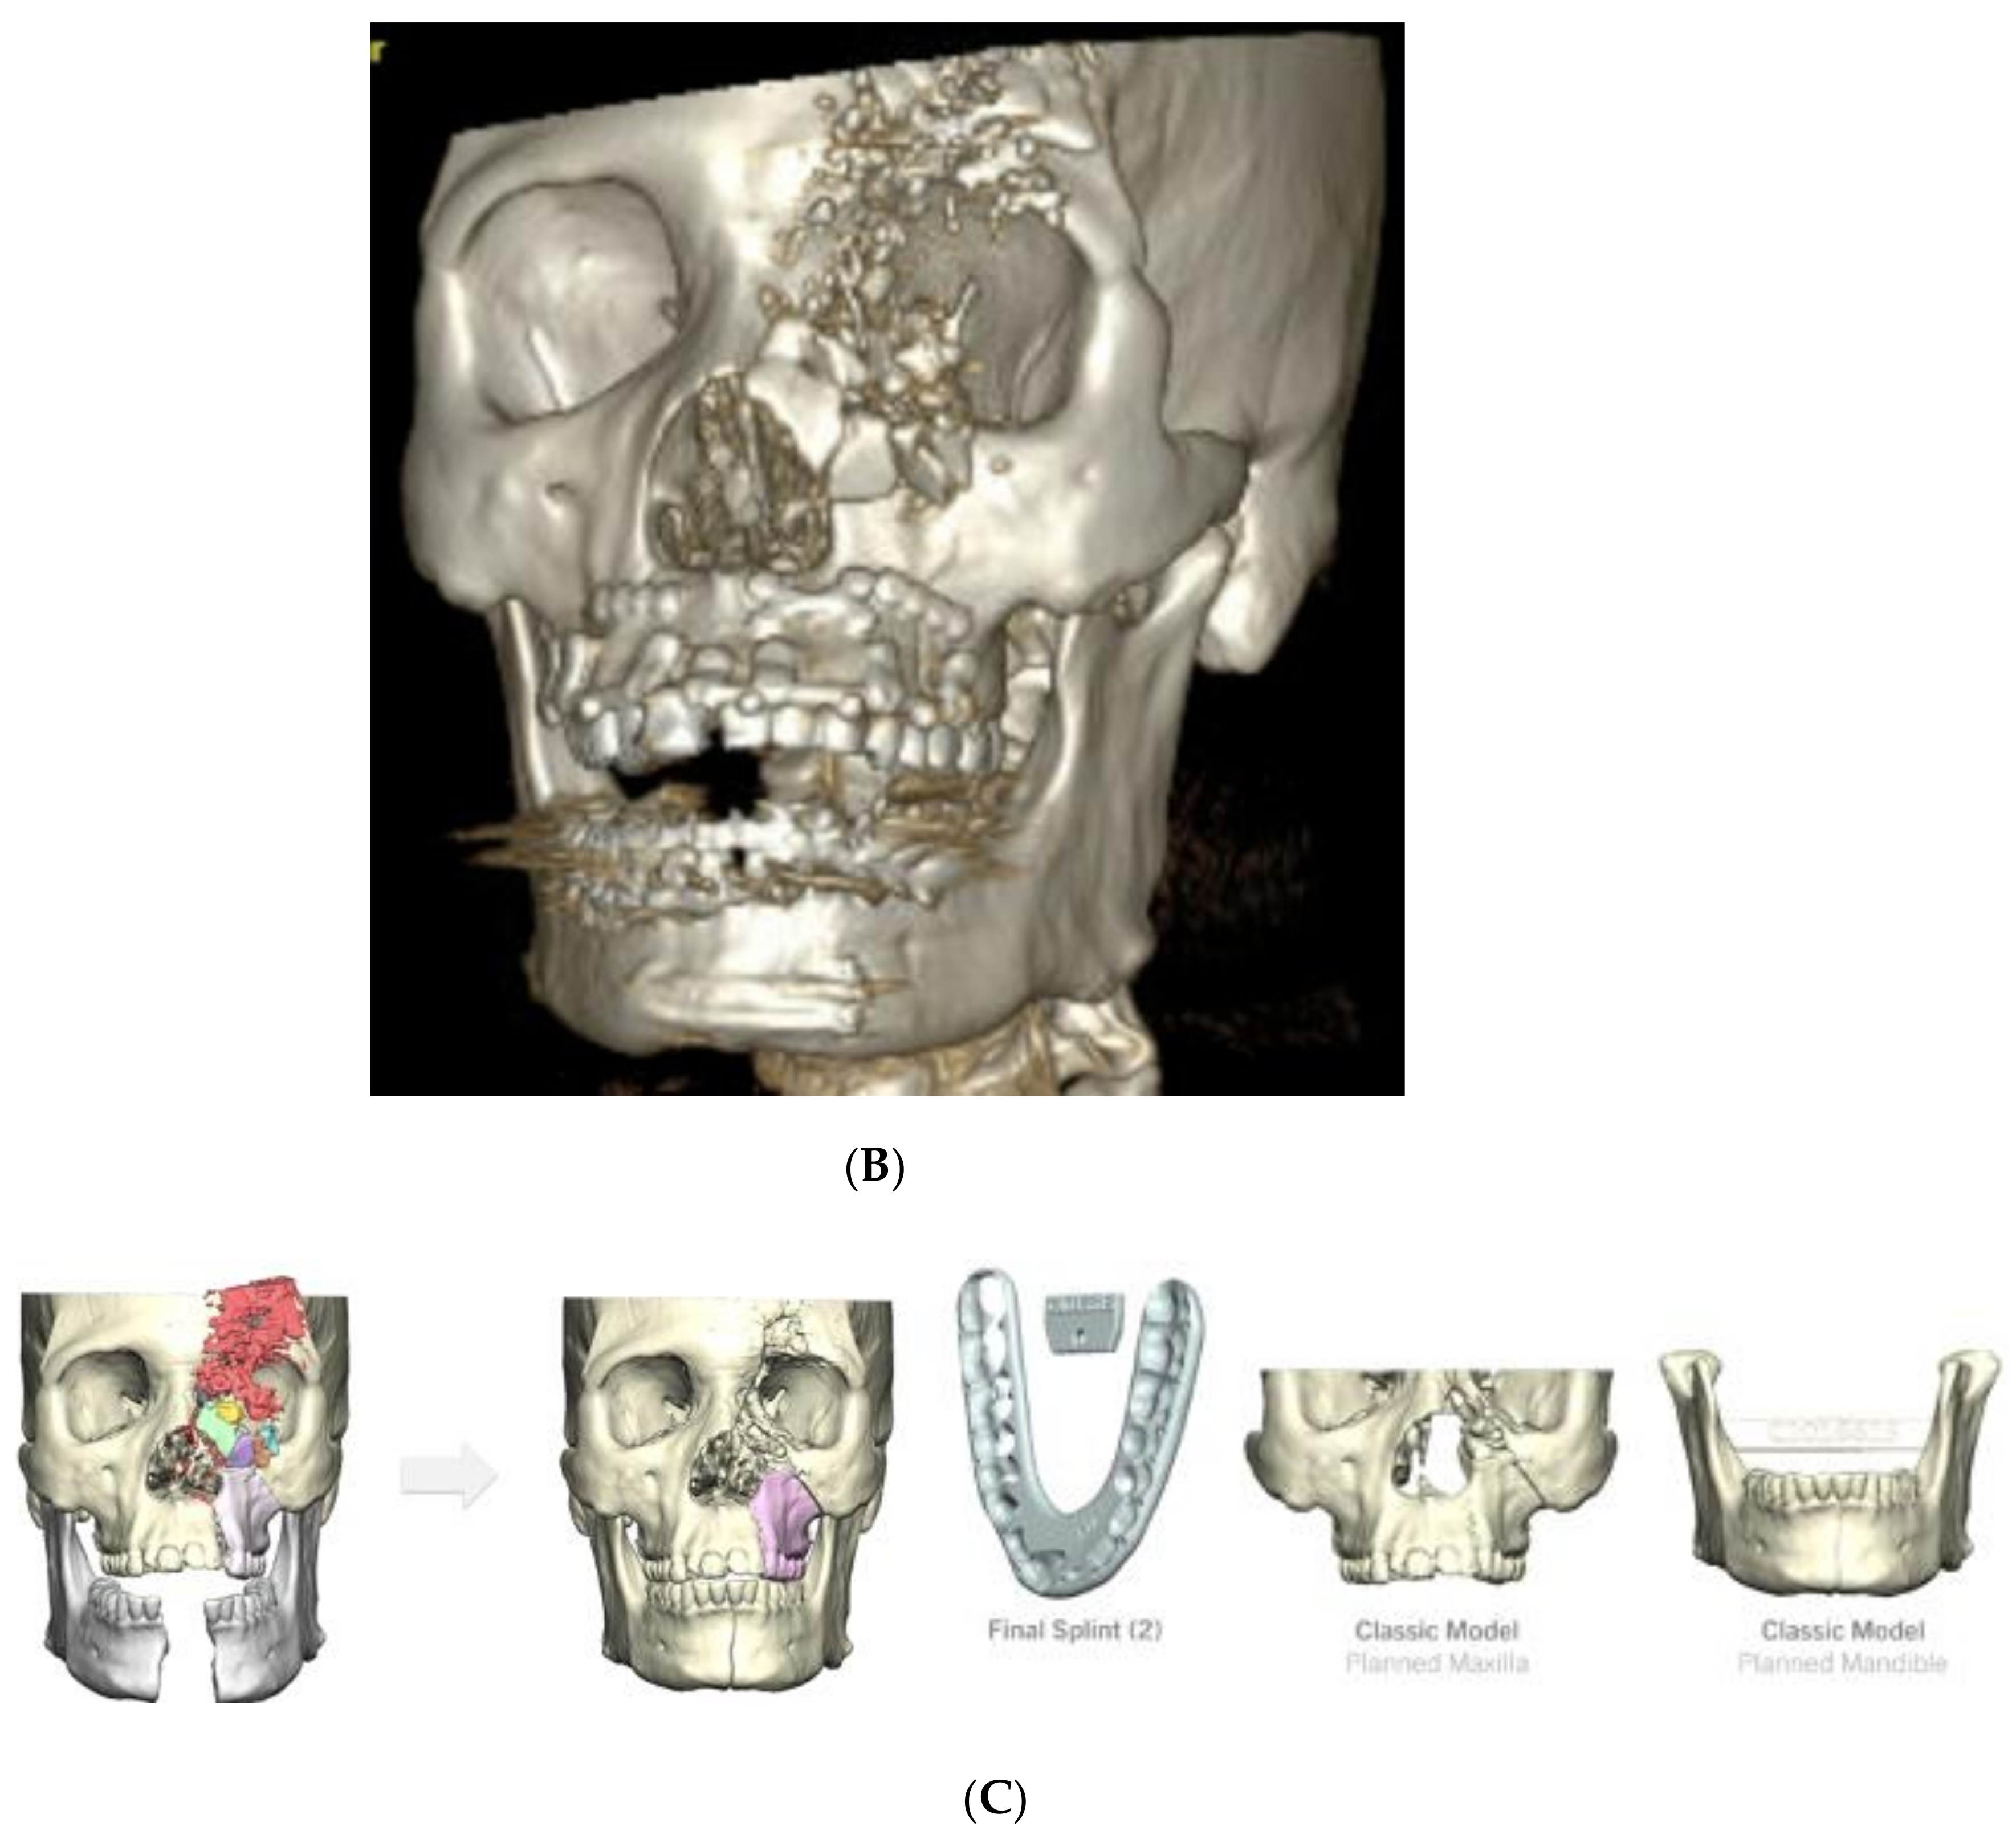

4.2. Case 2 (Occlusal Splint, 3D Model)

- Bilateral calvarial and skull base fractures;

- Comminuted left orbital fractures;

- Left Le Fort I/II/III maxillary fractures;

- A comminuted left maxillary fracture involving the left and right hard palate with a mobile palate segment;

- Bilateral comminuted, displaced, open mandibular body fractures;

- Bilateral comminuted nasal fractures.